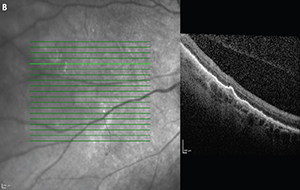

![]() | Figure 3. Intraoperative still image of the biopsy site shows where endolaser was applied to barricade the nasal area up to the far periphery. A more confluent circle of laser was applied to immediately surround the area of retinitis and deep endodiathermy was applied to the inner laser barricade to help initiate the retinectomy |